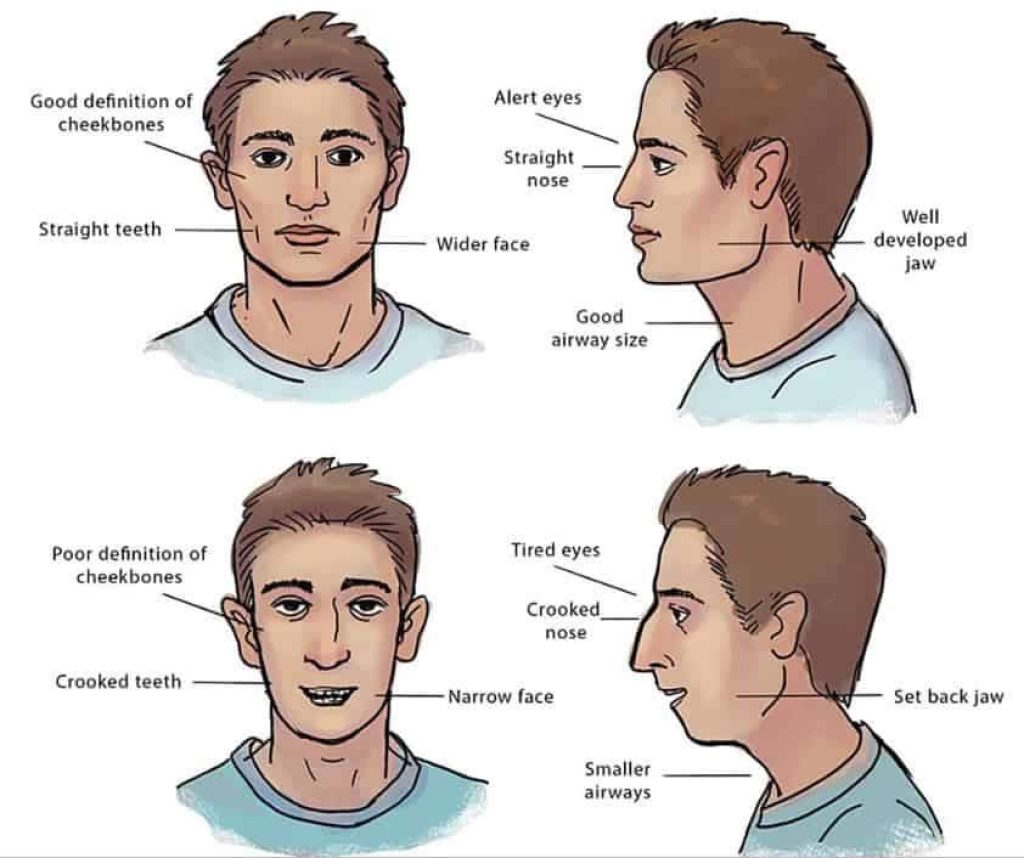

Small jaws aren’t genetic — they’re a modern problem often linked to lifestyle factors during childhood.

- Mouth breathing, often linked to allergies or blocked nasal breathing, leading to longer and narrower facial development

Aesthetically, longer and narrower facial development can result in a weaker jaw profile compared to healthier, wider jaw development.